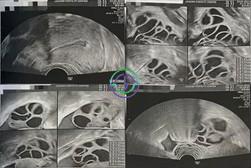

促排第 11 天 — 几乎所有卵泡已达目标大小;准备取卵

超声结果

右侧卵巢:卵泡大小 21,20,20,21,19,19,19,18,18,18,17,16,15,14 mm → 共 14 个卵泡

左侧卵巢:卵泡大小 22,20,20,20,20,20,19,19,18,17,17,17,17,16 mm → 共 14 个卵泡

在本病例中,卵巢刺激反应良好。卵泡从最初的小尺寸逐渐发育,到第 11 天时已有大量卵泡达到适宜大小(18–22 mm)。雌激素水平也持续升高,提示卵泡已准备好接受触发针注射和取卵。